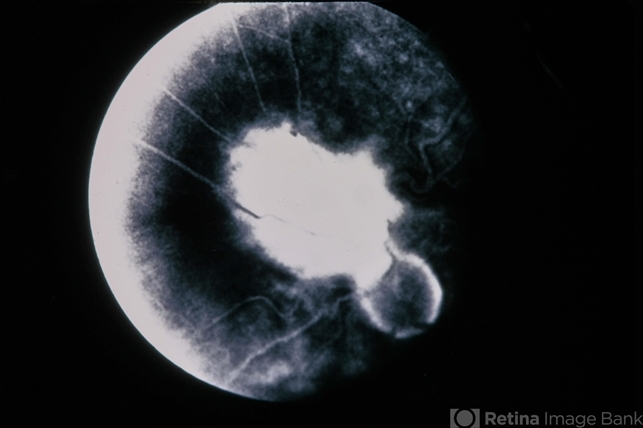

- Combined Retinal RPE Hamartoma

- combined hamartoma, retinal pigment epithelium (RPE) hamartoma

- 66-year-old white female, combined retinal & RPE hamartoma.